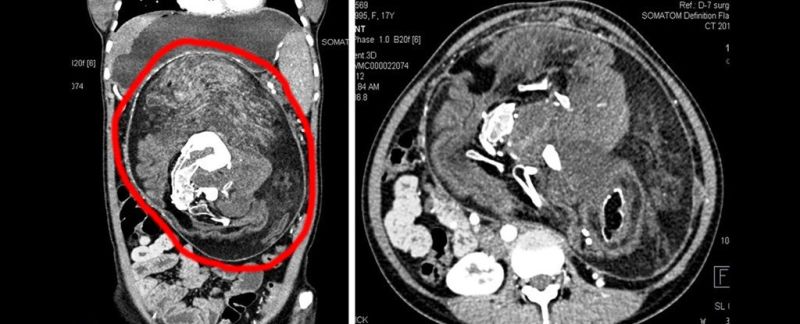

Acude a urgencias por un fuerte dolor de estómago y le encuentran los restos de su gemelo parcialmente formado

Los médicos no daban crédito a los resultados de los primeros análisis. Cuando una joven de 17 años en Patna, India, llegó a urgencias aquejada de un fuerte dolor en el estómago que había crecido hasta distorsionar su cavidad abdominal, los expertos parecían tenerlo claro: debía ser un tumor. Sin embargo, aquella masa tenía dientes.